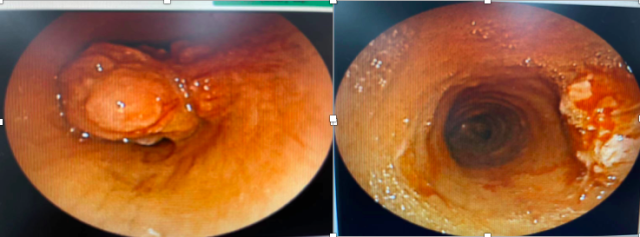

气管内肿瘤气管镜介入治疗前后对比。

该科吴健主任团队接诊后,予完善检查,充分评估病情,于第二天进行气管镜检查。术中发现施女士气管上端有一带蒂的菜花样肿瘤,堵塞气管管腔的90%,且肿瘤随呼吸动作上下翻滚。吴健主任果断运用气管镜介入技术,成功套除、消融该气管内新生物,切下的肿瘤送病理,患者呼吸困难症状立即缓解。